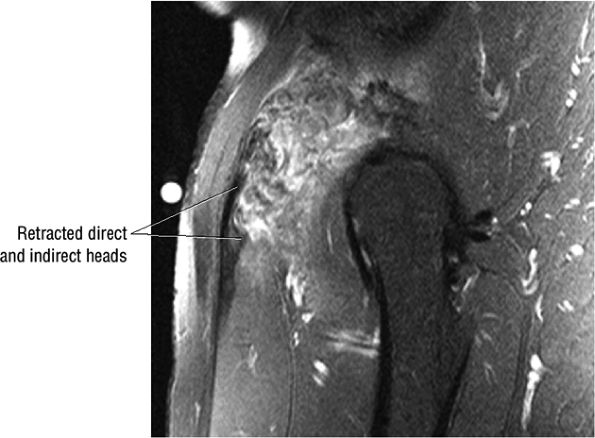

FIGURE 3.6 ● RECTUS FEMORIS The rectus femoris flexes the thigh (hip) and extends the leg (knee). Of the four quadriceps muscles (the vastus lateralis, vastus medialis, vastus intermedius, and rectus femoris), only the rectus femoris has an origin that crosses the hip joint. Soccer, football, and basketball players and track and field athletes are at risk for distal musculotendinous junction injuries and proximal intrasubstance tears of the musculotendinous junction of the indirect head of the rectus.

Grade 1: Minimal disruption of the musculotendinous junction (Fig. 3.106). Clinically, a grade 1 strain may simply result in a muscle spasm or cramp.

Grade 2: A partial tear with some intact musculotendinous fibers (Fig. 3.107). Clinically, there is discomfort during sports activity or training, but it usually resolves with rest.

Grade 3: Complete rupture of the MTU (Fig. 3.108)